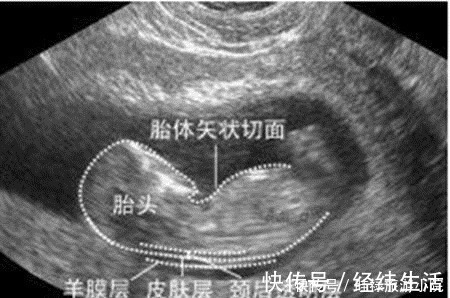

检查时间:怀孕早期到怀孕中期,一般在孕12周产检时检查。这项检查大概在孕11周6天时开始检查,又称为“胎儿颈透明膜厚度的检查”,这项检查对检查时间有严格要求,因而孕妈要提前预约好,按时去做检查。检查方法:通过B超来测量胎儿颈部后方透明膜的厚度,来初步判断胎儿神经管发育的情况,是否存在畸形。如果透明膜过厚,就可能提示:胎儿存在神经管发育的畸形。